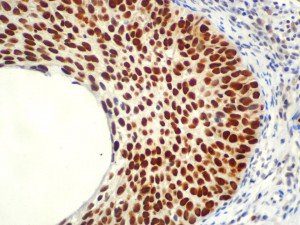

It is the ICU physician who is most likely to witness one of the deadliest manifestations of the abnormal immunological response, the cytokine storm syndrome (CSS). This response is also referred to by some as the cytokine release syndrome (CRS). CSS is characterized by continuous activation and expansion of macrophage and lymphocyte populations, which secrete large amounts of cytokines, causing the cytokine storm. This massive cytokine release is akin to hemophagocytic lymphohistiocytosis (HLH) disease, a syndrome characterized by initial unchecked and persistent activation of cytotoxic T lymphocytes and NK cells.

Clinical and laboratory manifestations of HLH include fever, enlarged liver and/or spleen, neurologic dysfunction, coagulopathy, liver dysfunction, cytopenias (i.e., low levels of erythrocytes, leukocytes, and/or platelets), hypertriglyceridemia, hyperferritinemia, hemophagocytosis, and eventually diminished NK cell activity as the immune system becomes progressively paralyzed. HLH can be familial (primary HLH) or secondary to another disease process (sHLH), such as rheumatic disease, in which it is referred to as macrophage activation syndrome (MAS, characterized by elevated ferritin).